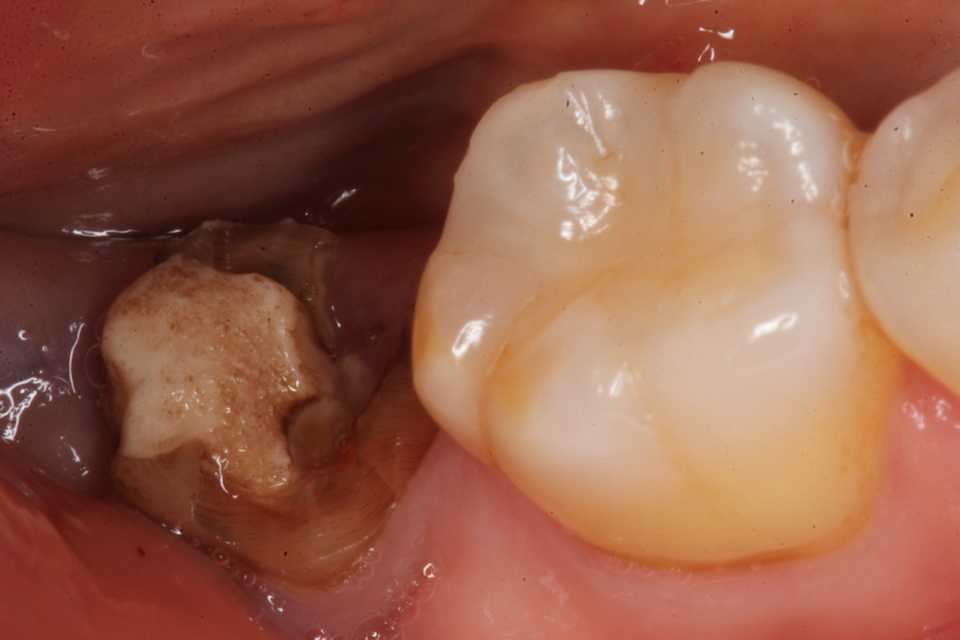

30代女性、右下7、Per、歯牙破折、歯根吸収?ほとんど抜けそうな(抜けている)状態で来られた。ご本人にお訊きしてもどうしてこうなったのか記憶にないそうだ。とりあえずレントゲン写真でのbefore/afterだが、近心の歯根が半分無くなっている。吸収されたのか、破折して破折片がどこかに行ってしまったのか、よく分からない。とりあえず抜いてみるしかない。beforeafter処置前はセラミック系の冠が装着されていたが、グラグラしている。冠は横から切断して除去した。歯根は前後(近遠心的)に破断していてグラグラしているのを確認した。どこまで健全歯質が残っているか軟化象牙質を削除しながら見てみたが、切削バーが届く範囲で健全歯質を確保するのはできなかった。抜歯してみないと正確なところは分からない。抜歯して直視下で見ないと軟化象牙質を除去し、健全歯質を出すことはできない。健全歯質の新鮮面を出さないとスーパーボンドは接着しないので、歯根の再建はできないということになる。抜歯再植は次回にすることにしてα-TCPで仮封鎖した。つづく

30代女性、右下7、Per、歯牙破折、歯根吸収?https://plaza.rakuten.co.jp/mabo400dc/diary/202509180000/抜いてみると複雑な欠損状態で、頬側の上の部分は歯根膜、骨膜等の細胞が少なかったので、生着しにくく使えないと判断した。頬側の部分に欠損がある。欠けたのか吸収されたのか分からない。吸収だとすれば自身の免疫系が自身の歯を異物と見做しての排除機転が働いているということなので、生着したとしても排除機転は止まらないだろう。舌側は歯根膜は残っている。頬側は80%の歯根面が失われている。歯根膜がないので生着しても歯槽骨はできない。強い咬合力には耐えられないだろう。綺麗にして接着剤が効くように歯質の新鮮面を出す。白いのはCR系のコア材。ピンク色は根管充填材。根尖付近は歯根膜が失われている。膿瘍があったことが分かる。根管充填材も除去して根尖口まで貫通させるここから歯根の折損部をスーパーボンドとCRで修復・再建していく過程。既成のポストを当ててみた。裏面(舌側)、歯根膜はほとんど残っている。内側だけで持たせている状況。上半分は歯根膜が無いので使えないと判断した。エッチング処理をしてスーパーボンドで修復根尖口も筆積み法で塞ぐCRも使い始める。舌側面CRで上半分を覆う次回は再植過程。つづく